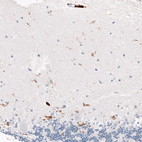

Immunohistochemistry analysis in human cerebral cortex and skeletal muscle tissues using AMAb91646 antibody. Corresponding CD163 RNA-seq data are presented for the same tissues.